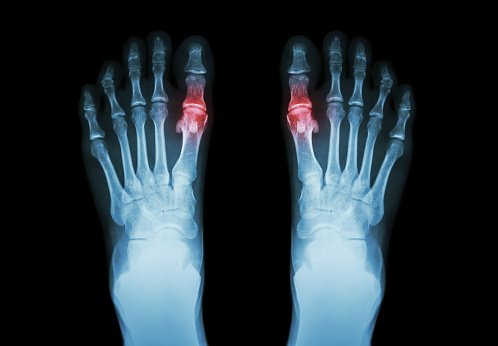

Riesgo de fractura por fragilidad entre pacientes con gota y el efecto de la terapia de disminución de urato

CMAJ, 14 de mayo de 2018 la gota no se asoció con un mayor riesgo de fractura. Los fármacos reductores de uratos prescritos al comienzo de la enfermedad, no poseen ni efectos adversos o beneficiosos sobre el riesgo a largo plazo de fractura.